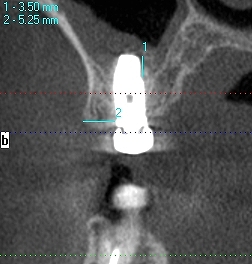

頬側は骨造成をしています頬側は

頬側は骨が3mm以上ないといけません

上顎洞への解剖距離が大切です

上顎洞を破ると別の問題が出ます

上顎洞を持ち上げたりします

頬側が骨幅が取れるケースと取れないケースもあります